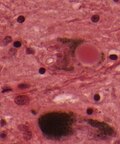

| Parkinson disease | alpha-synuclein | brainstem | parkinsonism | Lewy bodies in substantia nigra and locus coeruleus | [3] [4] |

- Lewy bodies (seen in Parkinson's Disease (PD), Dementia with Lewy bodies (DLB)) = round cytoplasmic eosinophilic body +/- pale halo.

- Lewy bodies and extracellular pigment in neuromelanin-containing nuclei (SN, LC, DVN) -> PD.

- Lewy bodies (in remaining neurons) - key feature.

- Eosinophilic cytoplasmic inclusion with "dense" (darker) core and pale (surrounding) halo.

- Consist of filaments composed of alpha-synuclein.